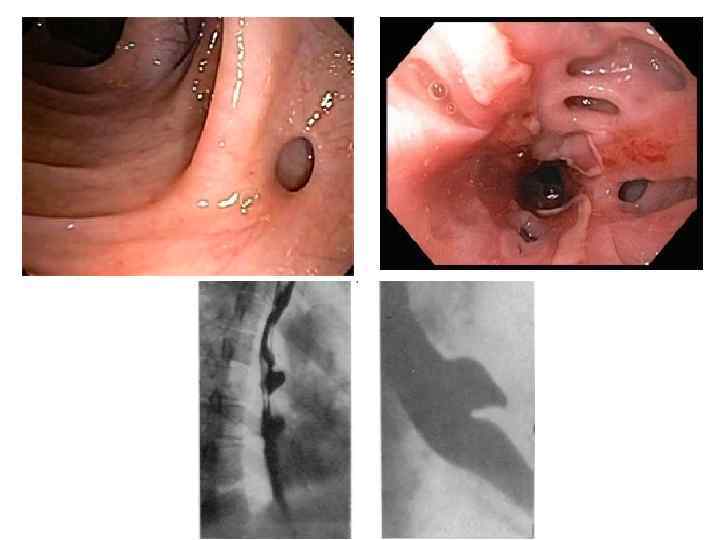

Бужирование пищевода • Рубцовый стеноз пищевода возникает через 1 -2 месяца. Если проводилось раннее бужирование, то образование стеноза происходит только у 4, 2 % больных, без профилактического бужирования – почти в 50 %. • Раннее бужирование начинают спустя 5— 10 дней (до 14 -го дня) после ожога. • Введенный в сужение буж оставляют в пищеводе на 15— 20 мин, а при тенденции к сужению — до 1 ч. На следующий день вводят на короткое время буж того же диаметра, а вслед за ним буж следующего номера, оставляя его в пищеводе на положенное время. При возникновении болезненной реакции, признаков недомогания, повышения температуры тела бужирование откладывают на несколько дней. • Ранее бужирование проводят ежедневно или через день в течение месяца даже при отсутствии признаков сужения пищевода, а затем в течение 2 мес по 1— 2 раза в неделю

Бужирование пищевода • Рубцовый стеноз пищевода возникает через 1 -2 месяца. Если проводилось раннее бужирование, то образование стеноза происходит только у 4, 2 % больных, без профилактического бужирования – почти в 50 %. • Раннее бужирование начинают спустя 5— 10 дней (до 14 -го дня) после ожога. • Введенный в сужение буж оставляют в пищеводе на 15— 20 мин, а при тенденции к сужению — до 1 ч. На следующий день вводят на короткое время буж того же диаметра, а вслед за ним буж следующего номера, оставляя его в пищеводе на положенное время. При возникновении болезненной реакции, признаков недомогания, повышения температуры тела бужирование откладывают на несколько дней. • Ранее бужирование проводят ежедневно или через день в течение месяца даже при отсутствии признаков сужения пищевода, а затем в течение 2 мес по 1— 2 раза в неделю

• Раннее бужирование у детей преследует цель предупреждения развития сужение просвета пищевода в фазе репаративных процессов рубцевания его пораженной стенки. По данным автора, начатое в первые 3— 8 дней после ожога бужирование не опасно для пострадавшего, так морфологически изменения в этот период распространяются только на слизистый и подслизистый слоя, и поэтому опасность перфорации минимальна. Показаниями для раннего бужирования служат нормальная температура тела в течение 2 -3 дней и исчезновение острых явлений общей интоксикации. Позже 15 -го дня с момента ожога бужирование становится опасным и для ребенка, так и для взрослого, так наступает фаза рубцевания пищевода, он становится ригидным и мало податливым, а стена не приобрела еще достаточной прочности.

• Раннее бужирование у детей преследует цель предупреждения развития сужение просвета пищевода в фазе репаративных процессов рубцевания его пораженной стенки. По данным автора, начатое в первые 3— 8 дней после ожога бужирование не опасно для пострадавшего, так морфологически изменения в этот период распространяются только на слизистый и подслизистый слоя, и поэтому опасность перфорации минимальна. Показаниями для раннего бужирования служат нормальная температура тела в течение 2 -3 дней и исчезновение острых явлений общей интоксикации. Позже 15 -го дня с момента ожога бужирование становится опасным и для ребенка, так и для взрослого, так наступает фаза рубцевания пищевода, он становится ригидным и мало податливым, а стена не приобрела еще достаточной прочности.

• Лечебное бужирование следует применять не ранее 7 нед после ожога, т. к. при бужировании пищевода в сроки от 2 до 6 нед после ожога происходит разрушение бужом грануляций и свежей соединительной ткани. В этот период наиболее часто отмечают перфорации пищевода.

• Лечебное бужирование следует применять не ранее 7 нед после ожога, т. к. при бужировании пищевода в сроки от 2 до 6 нед после ожога происходит разрушение бужом грануляций и свежей соединительной ткани. В этот период наиболее часто отмечают перфорации пищевода.

• • При пальпаторном введении бужа больной сидит со слегка наклоненной вперед головой. Врач левым указательным пальцем отдавливает корень языка вперед и вниз, а правой рукой, строго придерживаясь средней линии, вводит буж в нижний отдел глотки, а затем в пищевод (рис. 289). При этом в какой-то момент врач ощущает препятствие, соответствующее верхней границе сужения. На буже делается отметка о расстоянии до начала сужения. Если буж не входит в стриктуру, последовательно вводятся бужи меньших размеров до тех пор, пока один из них не пройдет в сужение. А - правильное положение головы; Б - неправильное положение головы.

• • При пальпаторном введении бужа больной сидит со слегка наклоненной вперед головой. Врач левым указательным пальцем отдавливает корень языка вперед и вниз, а правой рукой, строго придерживаясь средней линии, вводит буж в нижний отдел глотки, а затем в пищевод (рис. 289). При этом в какой-то момент врач ощущает препятствие, соответствующее верхней границе сужения. На буже делается отметка о расстоянии до начала сужения. Если буж не входит в стриктуру, последовательно вводятся бужи меньших размеров до тех пор, пока один из них не пройдет в сужение. А - правильное положение головы; Б - неправильное положение головы.

• Бужирование через рот (вслепую). При небольшом сужении пищевода. При сформировавшихся рубцовых сужениях следует ежедневно или каждые 2 дня вводить буж возрастающего размера (до 3840 го). Затем бужируют 2 раза в неделю и 1 раз в месяц в течение года.

• Бужирование через рот (вслепую). При небольшом сужении пищевода. При сформировавшихся рубцовых сужениях следует ежедневно или каждые 2 дня вводить буж возрастающего размера (до 3840 го). Затем бужируют 2 раза в неделю и 1 раз в месяц в течение года.

• Бужирование под контролем эзофагоскопа. • Бужирование по металической струне-проводнику.

• Бужирование под контролем эзофагоскопа. • Бужирование по металической струне-проводнику.